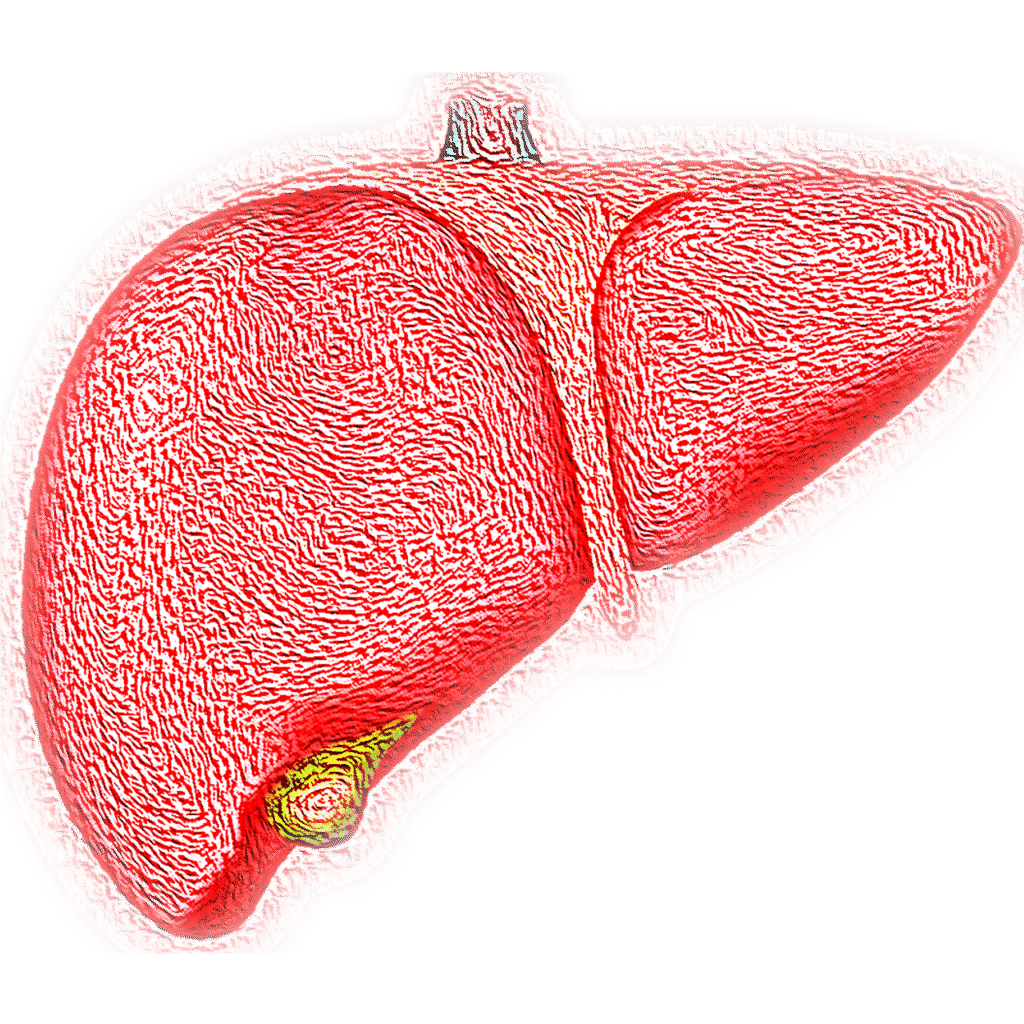

A májad is ember – csak épp kicsit túlórázik minden nap

A máj nemcsak egy belső szerv, hanem egy igazi multitasking bajnok: egyszerre főkönyvelő, méregtelenítő, energiamérnök és raktáros. Gyakorlatilag a tested szürke eminenciása, aki csendben végzi a dolgát… amíg túl nem terheled pizzával, cukros üdítőkkel és kanapén töltött délutánokkal.

Szóval ha a tested egy rockbanda lenne, a májad lenne a dobos – és mindenki tudja: ha a dobos kidől, az egész buli szétesik. Ne hagyd cserben a ritmust – szeresd a májadat, mert ő minden nap szeret téged. Csak kicsit csendesebben. 😊

A máj szerepe a mindennapi egyensúlyban

A máj egyfajta belső „vegyészlabor”, amely minden étkezés után aktív működésbe lép. A belekből érkező tápanyagok szinte teljes mennyisége rajta keresztül áramlik. Itt zajlik le többek között:

A máj állapota közvetlenül befolyásolja az energiaszintet, a közérzetet és a szervezet anyagcseréjét. Bár a modern életmód sok kihívást tartogat, a kiegyensúlyozott étrenddel, a tudatos mozgással és a mértékletes szokásokkal sokat tehetünk azért, hogy ez a szerv hosszú távon optimálisan működjön.